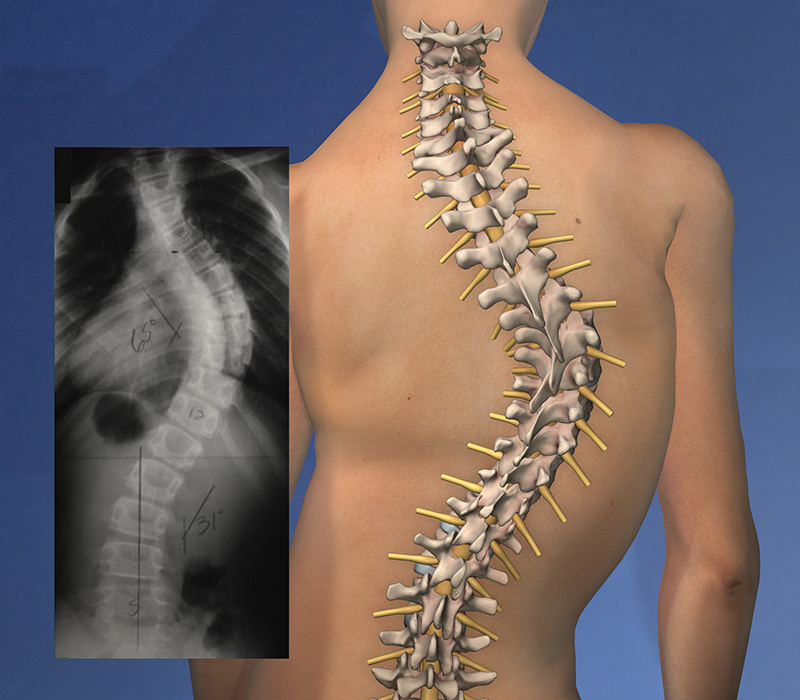

Фото из открытых источников

Сколиоз — это искривление позвоночника в трёх плоскостях с обязательной ротацией позвонков (если ротации нет, то это уже не сколиоз).

Важно понимать, что это деформация костных структур, а не просто следствие разного тонуса мышц, как вы могли слышать. При этом наиболее распространённый диагноз — "идиопатический сколиоз" — ставится в 70% случаев, и его происхождение до сих пор остаётся загадкой.